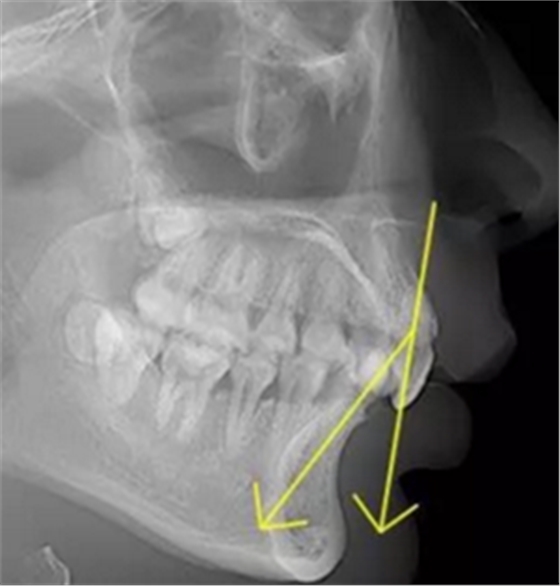

正常情況下,我們的上前牙是蓋在下前牙唇側(cè)3mm內(nèi)的,上下切牙牙軸交角為125°左右,

但前牙閉鎖合是上前牙下垂伸長,內(nèi)扣完全鎖住了下切牙,正面觀時我們??床坏较虑醒?,下切牙則常擁擠伸長咬到了上腭內(nèi)的牙齦上,上下前牙發(fā)生的交角幾近180°。

正常前牙交角

前牙閉鎖合交角